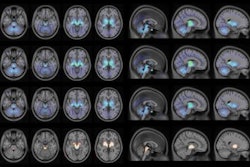

The study shows how the location of abnormal tau protein aggregates in parts of the brain signaled which particular condition patients had, results that were confirmed on biopsies and autopsies.

Uptake in the brain with F-18 PM-PBB3 was shown to be approximately twice as high as for C-11 PBC, according to the study. The authors also reported that PET images show the stability of the new probe in patients with dementia in contrast with low retention in healthy controls.

"The clearance of [F-18 PM-PBB3] was profoundly slowed in tau-burdened areas of the AD and [progressive supranuclear palsy] brains, conceivably reflecting the specific radioligand binding to tau aggregates," Higuchi et al wrote.

Based on PM-PBB3-positive tau deposits, it's possible to make clear separations between disorders, which has not been possible with other tau PET probes and other imaging modalities, such as volumetric MRI, the authors wrote. This "paves the way for the construction of a biomonitoring system for the selection of an adequate disease-modifying therapeutic," according to Higuchi et al.